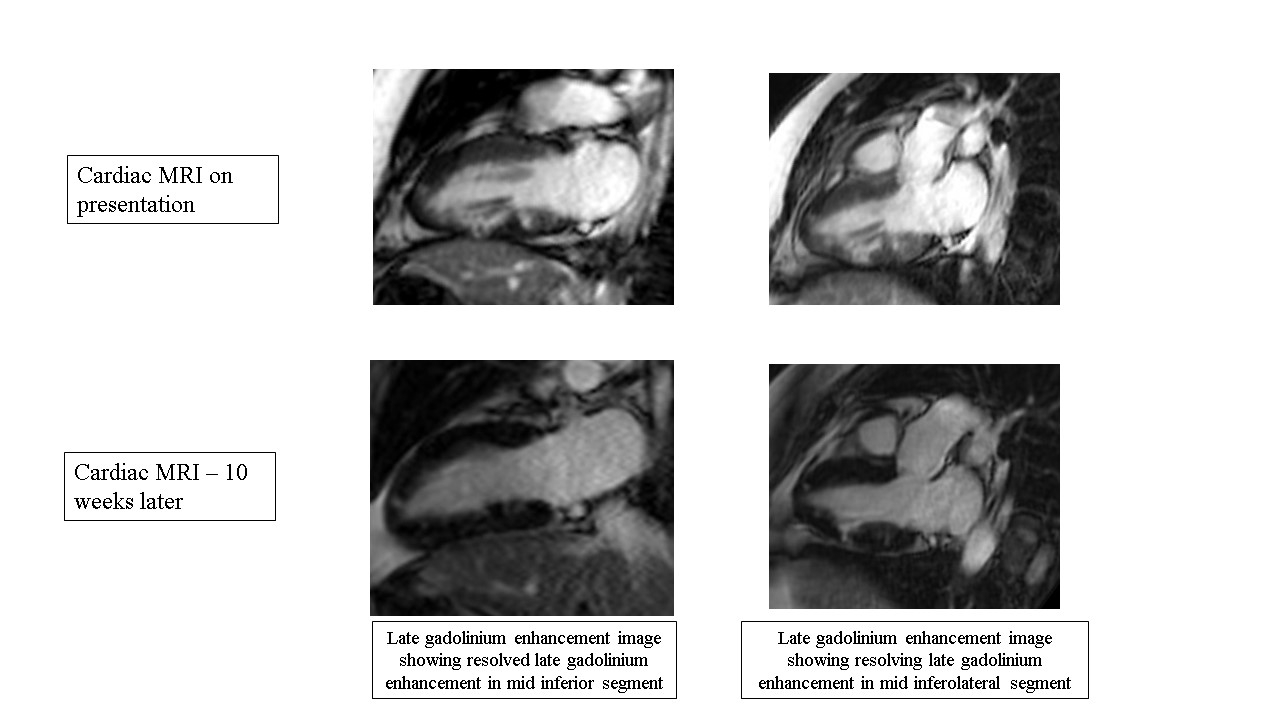

Cardiac MRI (CMR) findings demonstrated late gadolinium enhancement (LGE) of the mid-inferior segment of the left ventricle with moderate hypokinesis. Patient was treated with a short course of steroids. Repeat CMR 10 weeks later showed resolving LGE in the mid-inferior segment of the left ventricle.

CMR and duodenal biopsy demonstrated findings consistent with rare manifestation of HES with muti-organ inflammation as evident by left ventricular LGE, duodenal biopsy, and peripheral eosinophilia. Initial management involves prompt initiation of immunosuppressive therapy to mitigate eosinophilic infiltration and end-organ damage. Diagnostic modalities such as tissue biopsy, advanced imaging, and laboratory testing play crucial roles in confirming the diagnosis. Follow-up CMR can help follow the response treatment and rule-out confounding disease processes, as seen in our case. In conclusion, HES is a rare disorder with variable presentations. Eosinophilic myocarditis, a life-threatening sequala of HES, should be considered as a differential in patients that develop heart failure symptoms and eosinophilia after SCT.